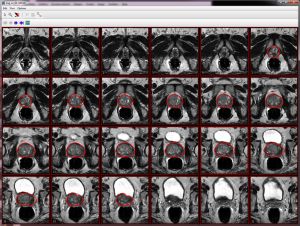

We use the semi-automatic segmentation dialog to segment the MRI prostate image. Before proceeding, please, make sure you open 3 orthogonal prostate images with VOIs - img_ax_83.xml and voi_ax_83.xml, img_sag_83.xml and voi_ax_sag.xml, and img_cor_83.xml and voi_cor_83.xml.

Note that the drawn VOIs slice numbers are automatically populated in the dialog box.

For each named VOIs based mask, the console window shows the number of voxels and volume. Created VOIs are used for the surface reconstruction step. Each VOI contour has 100 points.

Axial image VOIs: number of voxels = 333795 volume = 74871.586 mm^3 Sagittal image VOIs: number of voxels = 340633 volume = 76405.41 mm^3 Coronal image VOIs: number of voxels = 320149 volume = 71810.766 mm^3 time elapse = 1 mins 55 sec